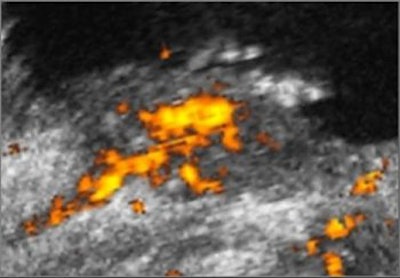

Freehand scanning was used for 3D data acquisition, and surface rendering and multiplanar reconstruction for 3D data analysis. Power Doppler ultrasound was used to differentiate the extent of infiltration. The criteria for staging were based on the vascularity of the tumor's basement. The gold standard was the histomorphology results.

| Power Doppler ultrasound criteria for staging vascularity of the tumor basement. Above, submucosal vessels; second, half muscle wall vascular. Below, whole muscle wall vascular; second image, few vessels in the perivesical walls; third image, massive flow in the perivesical fat. Images courtesy of Dr. Veronika Gazhonova, Russian President Medical Center and Russian State Medical University. |